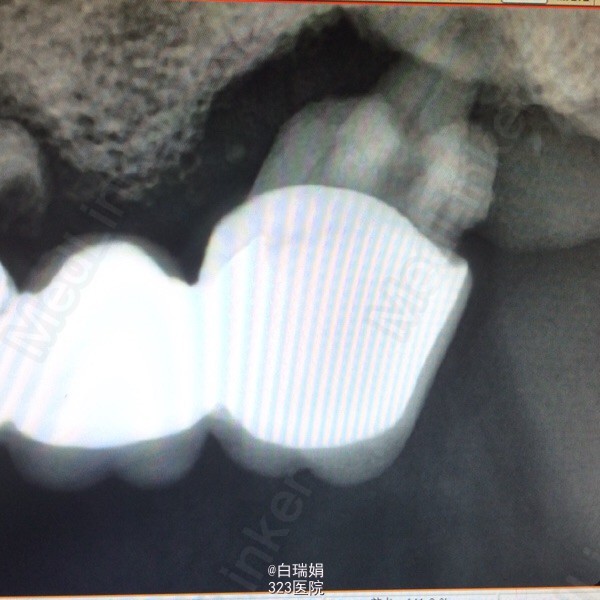

检查:左上3至左上7烤瓷联冠,松动2度,左上3、4、5、7叩诊(➕),左上7腭侧牙根吸收至根中1/3,右上4至右上7缺失,缺牙区牙槽嵴尚可,无明显骨突骨刺;X线示左上3、4、5牙周膜间隙增宽,根尖区低密度影像,左上5远中牙槽骨吸收至根中1/3,左上7牙槽骨吸收至根尖。